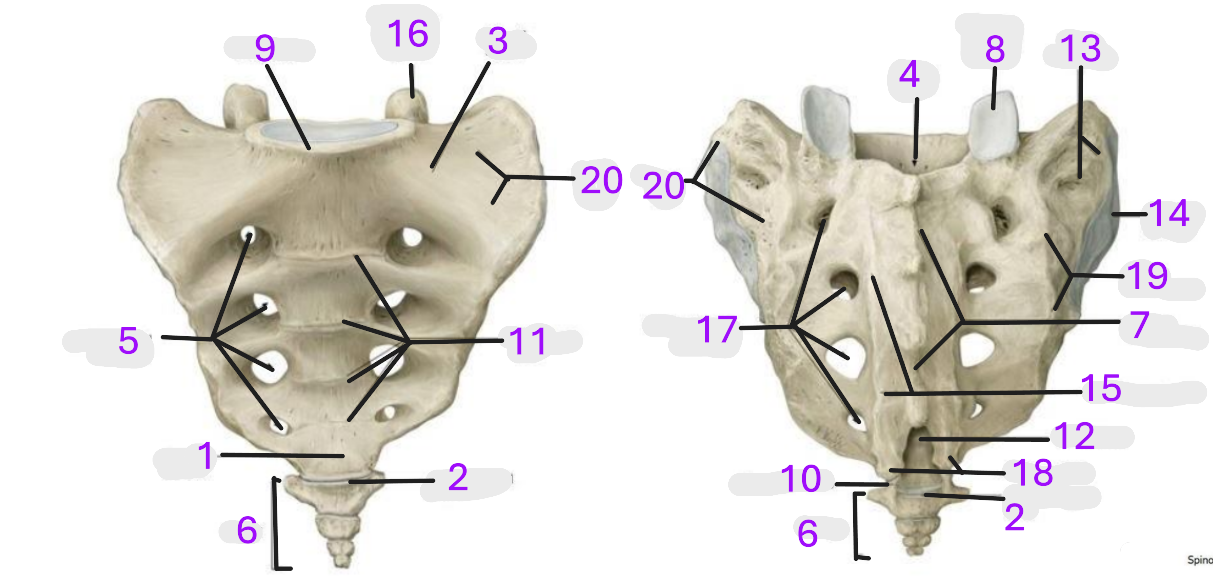

Where is the apex of sacrum

1

Where is the sacrococcygeal joint

2

Where is the wing of sacrum

3

Where is the sacral canal

4

Where is the anterior sacral foramina

5

Where is the coccyx

6

Where is the median sacral crest

7

Where is the superior articular facet

8

Where is the promontory

9

Where is the coccygeal cornu

10

Where is the transverse lines

11

Where is the sacral hiatus

12

Where is the sacral tuberosity

13

Where is the auricular surface

14

Where is the medial sacral crest

15

Where is the superior articular process

16

Where is the posterior sacral foramina

17

Where is the sacral cornua

18